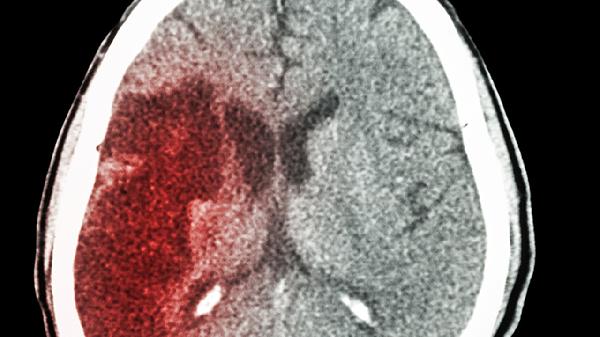

中风后遗症可能与脑组织缺血坏死、神经功能缺损有关,常见肢体麻木、语言障碍等症状。舒脑欣滴丸可作为辅助治疗药物促进侧支循环建立。康复期需配合针灸、功能训练等综合干预。

使用舒脑欣滴丸期间应监测血压变化,避免突然体位改变。饮食宜清淡,适当补充核桃、深海鱼等富含不饱和脂肪酸的食物。保持规律作息和适度运动有助于改善脑循环。若症状持续不缓解或出现新发神经系统症状,应及时就医复查脑部CT或核磁共振成像。